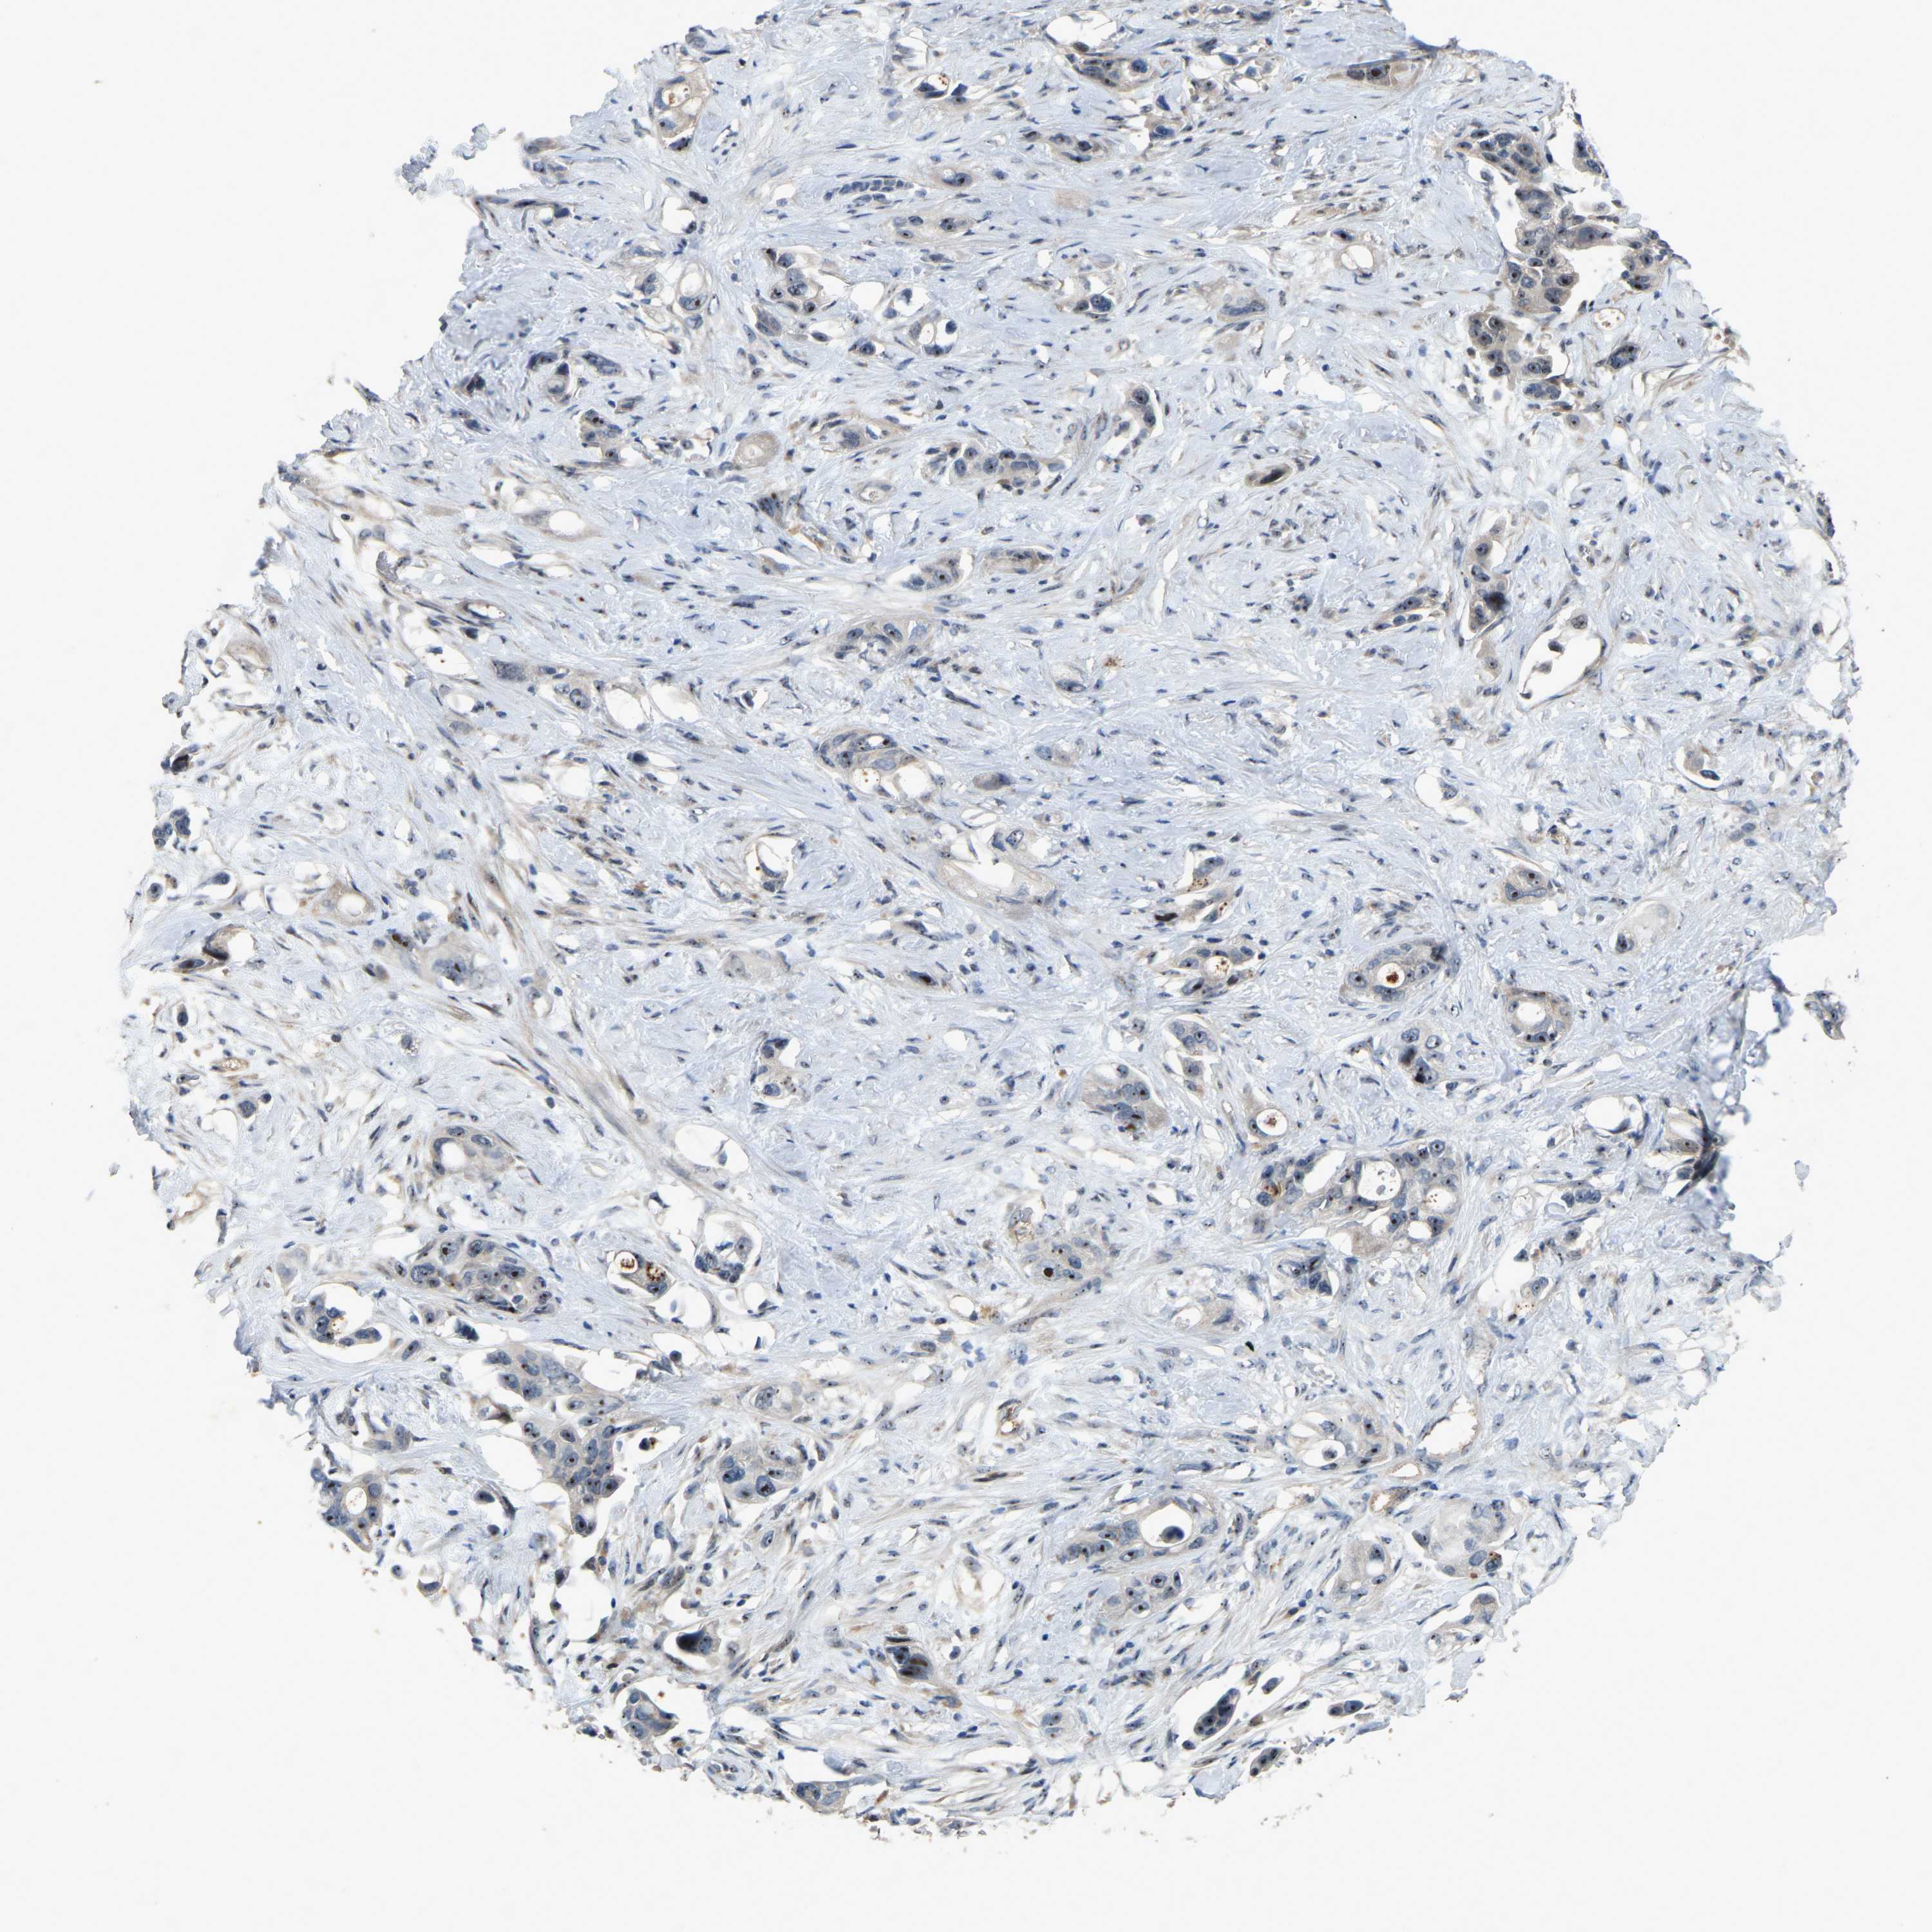

PANCREATIC CANCER - Protein expressioni

A mouse-over function shows sample information and annotation data. Click on an image to view it in a full screen mode. Samples can be filtered based on level of antibody staining by selecting one or several of the following categories: high, medium, low and not detected. The assay and annotation is described here.

Note that samples used for immunohistochemistry by the Human Protein Atlas do not correspond to samples in the TCGA dataset.

Antibody stainingi

Antibody staining in the annotated cell types in the current human tissue is reported as not detected, low, medium, or high, based on conventional immunohistochemistry profiling in selected tissues. This score is based on the combination of the staining intensity and fraction of stained cells.

Each image is clickable and will lead to virtual microscopy that enables deeper exploration of all samples and also displays staining intensity scores, fraction scores and subcellular localization as well as patient and tissue information for each sample.

Antibody HPA018840

Antibody HPA018909

Antibody CAB002684

Staining

High

Medium

Low

Not detected

Intensity

Strong

Moderate

Weak

Negative

Quantity

>75%

75%-25%

<25%

None

Location

Nuclear

Cytoplasmic/membranous

Cytoplasmic/membranous,nuclear

Adenocarcinoma, NOS

Adenocarcinoma, metastatic, NOS